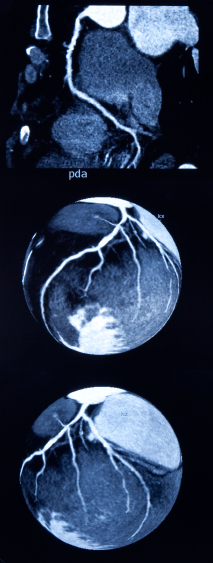

Ангиография фото

Диагностические процедуры для рентгеновских кровеносных сосудов. Краска вводится в сосуд с помощью катетера, который позволяет сосудистых структур для визуализации. Эта процедура может определить завалов и других проблем, препятствующих с потоком крови.